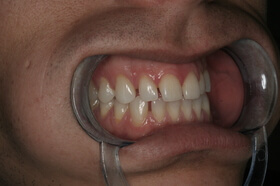

Agresszív fogágybetegség miatt kialakult frontfog elmozdulás – elülső nézet

Agresszív fogágybetegség miatt kialakult frontfog elmozdulás – oldalnézet